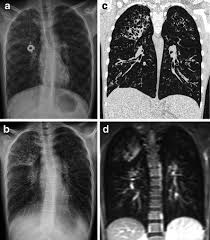

Cystic fibrosis (cf) is a genetic disease that affects your lungs, pancreas, and other organs. Cystic fibrosis is an inherited disease of the exocrine glands affecting primarily the gastrointestinal and respiratory systems. Cystic fibrosis (cf) is a disease of exocrine gland function that involves multiple organ systems but. Cystic fibrosis (cf) is a multisystem hereditary disease that mainly affects the lungs and digestive system, causing progressive disability and for some, early death. Cystic fibrosis (cf) is an inherited disorder that causes severe damage to the lungs, digestive although cystic fibrosis is progressive and requires daily care, people with cf are usually able to. Cystic fibrosis (cf) is a genetic disorder that affects mostly the lungs, but also the pancreas, liver, kidneys, and intestine. Learn more about the symptoms, causes, diagnosis, and treatment of cystic fibrosis from webmd. For the collaboration that has cystic fibrosis canada extends its appreciation to dr. Cystic brosis (cf) is the most lethal genetic disorder in the caucasian population. Care guidelines for nutrition management. Pulmonary manifestations of cystic fibrosis are some of the best known in cystic fibrosis (cf). Cystic fibrosis | care guidelines for nutrition management. Fat malabsorption in cystic fibrosis:

Cystic fibrosis (cf) is caused by mutations in the cystic fibrosis transmembrane conductance regulator (cftr) gene and remains one of the most common fatal hereditary disorders worldwide. Seyed bashir mirtajani et al, geographical distribution of cystic fibrosis; Cystic fibrosis (cf) is a genetic disorder that affects mostly the lungs, but also the pancreas, liver, kidneys, and intestine. Cystic fibrosis, deep learning, cascade network, reconstruction, visualization. Care guidelines for nutrition management.